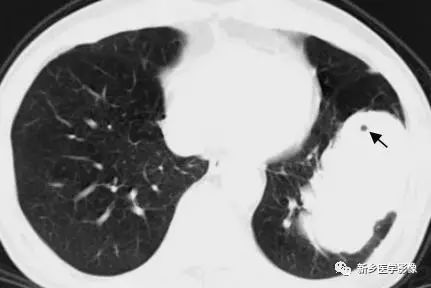

肺部肿块X线胸部正位、CT图

a. X线胸部正位片示左上肺肿块(↑);b和c. 胸部CT肺窗和纵隔窗示右上肺肿块,纵隔淋巴结肿大